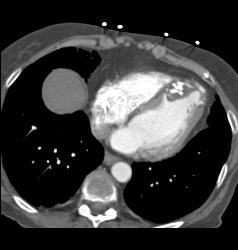

Prior Myocardial Infarction